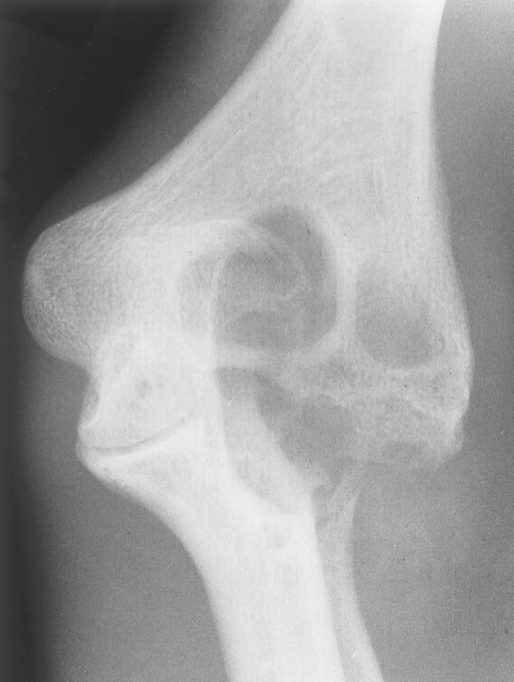

hemophilia

is an inherited (by a sex-linked recessive gene) anomaly of blood coagulation that appears clinically only in males.

easily bruising externally and internally